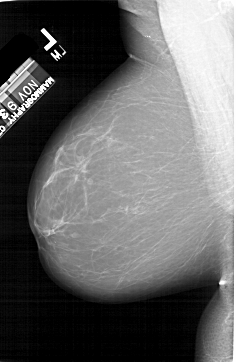

A_1412_1.RIGHT_CC

RIGHT_CC LINES 6631 PIXELS_PER_LINE 3961 BITS_PER_PIXEL 12 RESOLUTION 43.5 OVERLAY

FILE: A_1412_1.RIGHT_CC.OVERLAY

TOTAL_ABNORMALITIES 1

ABNORMALITY 1

LESION_TYPE MASS SHAPE IRREGULAR MARGINS CIRCUMSCRIBED

ASSESSMENT 4

SUBTLETY 5

PATHOLOGY BENIGN

TOTAL_OUTLINES 1

BOUNDARY